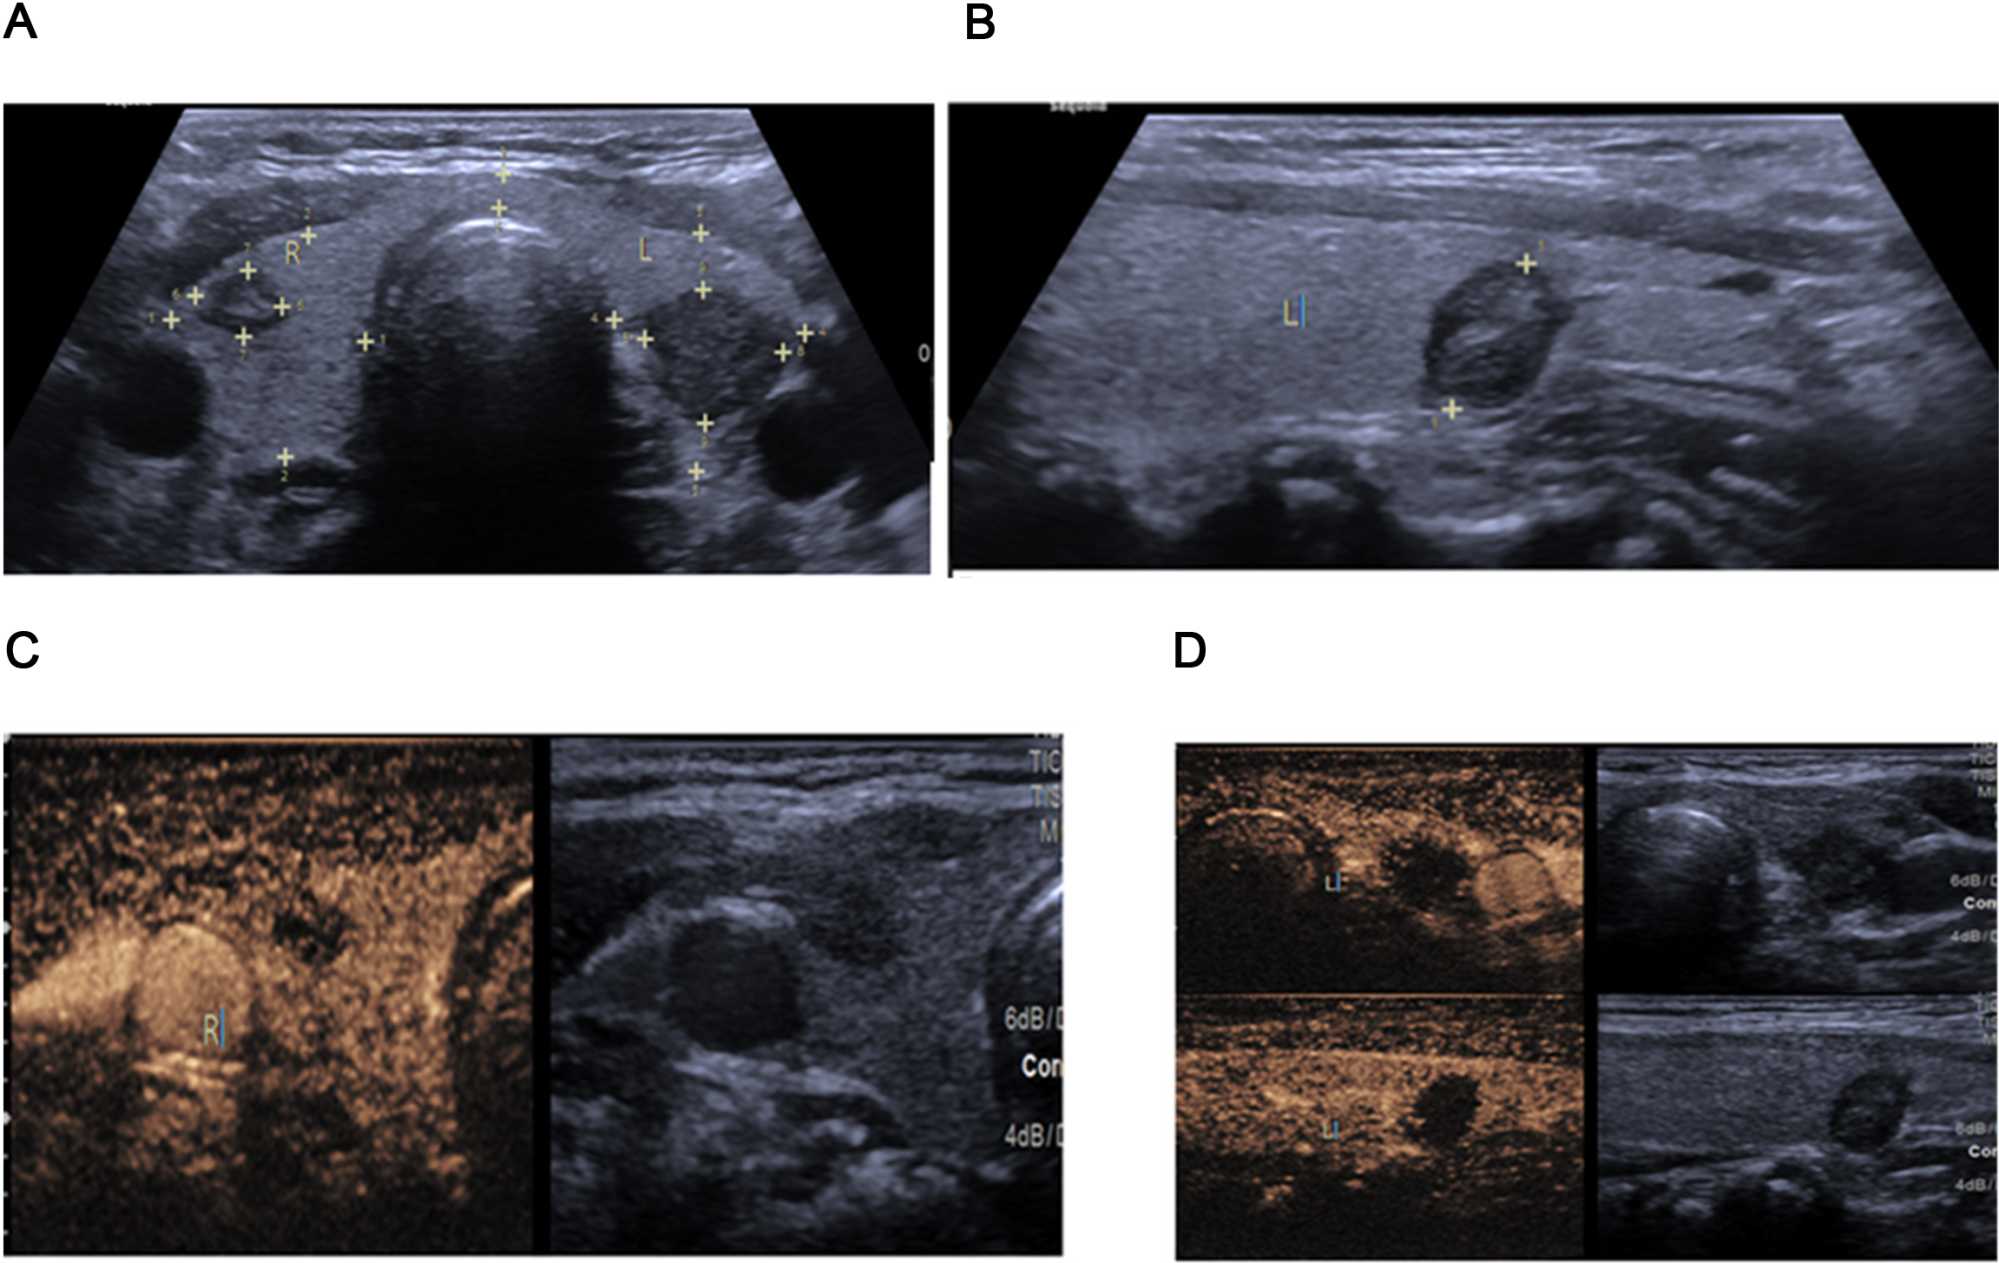

The primary outcome of this study was nodule inactivation following RFA. Of the 72 patients, 51 (70.8%) had complete nodule inactivation, while 21 (29.2%) had partial inactivation. Figure 2 shows nodule images of 2 patients before and after RFA. The two groups of patients had no significant differences in terms of age, gender, nodular diameter and volume (all p > 0.05). Those with complete inactivation had more calcification (p = 0.040), while those with partial inactivation had more vascularity (p < 0.001). Table 2. Analysis of changes in thyroid hormone levels between the two groups over a 6-months period showed no significant difference, although slight increase in TSH levels were seen within groups over the same period. Table 3. Figures 2-4 show sonographic images of a benign nodule pre RFA, a partially inactivated nodule and a completely inactivated nodule respectively.

Figure 3. A benign nodule in the right thyroid lobe based on the cytological results. The sonographic features included (A) wider than tall orientation, heterogeneous-hypoechoic solid mass, clear lobulated margins on grayscale mode (B) Addition of color Doppler showing peripheral color flow. (C, D) Application of CEUS shows peripheral enhancement. This was a partially inactivated benign thyroid nodule after RFA: Radiofrequency Ablation, CEUS: contrast-enhanced ultrasound.